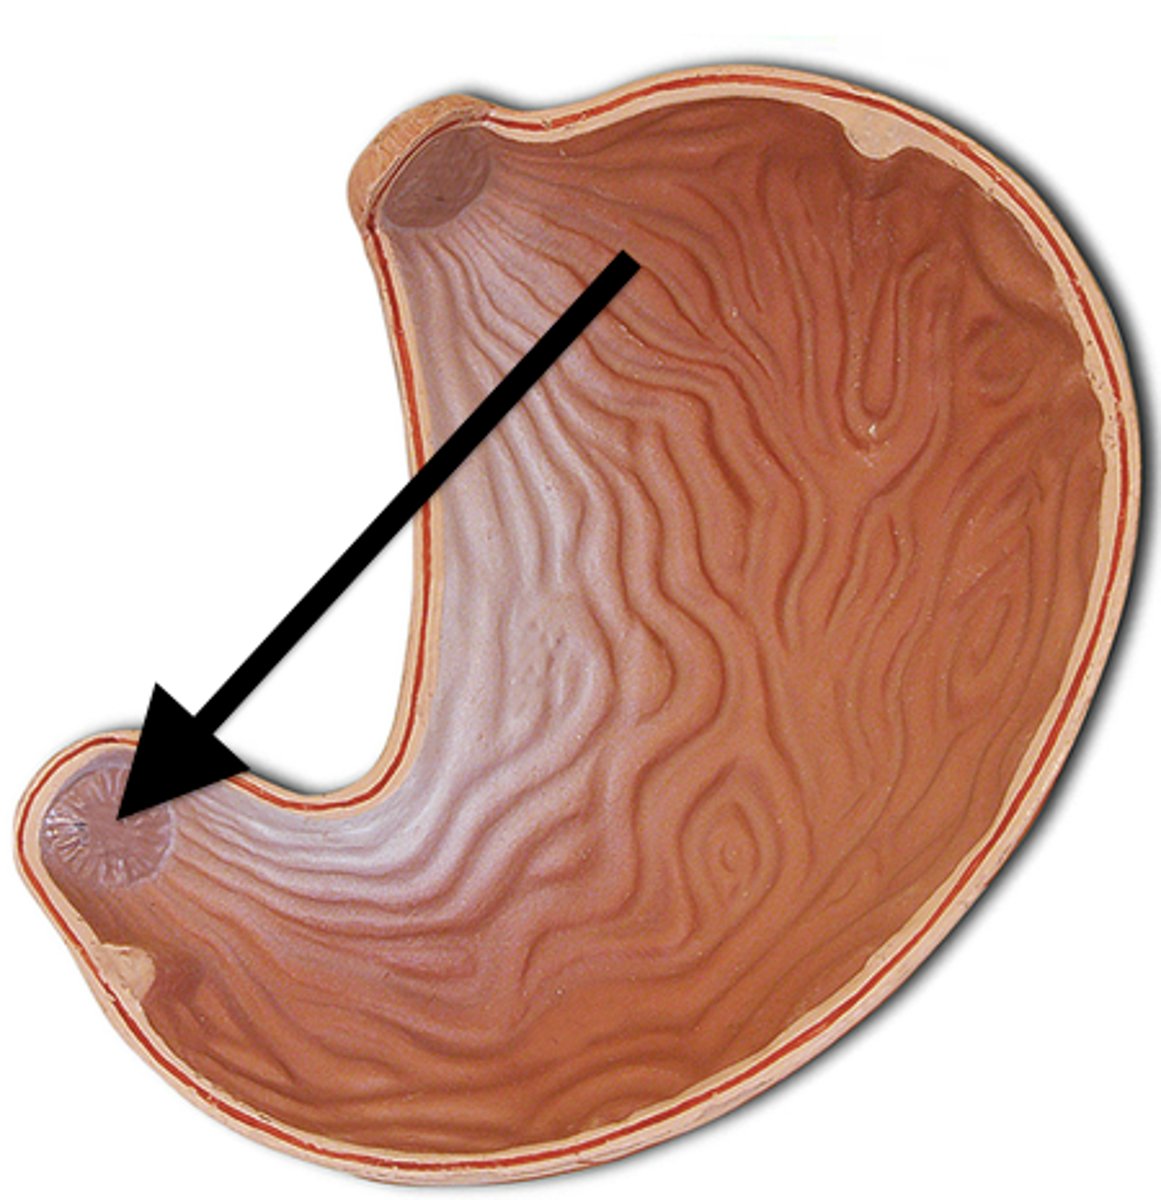

cardiac stomach (histology)

simple columnar epithelium

what kind of epithelium lines the mucosa of the cardiac stomach?

gastric pit (cardiac stomach)

lumen (cardiac stomach)

mucosa (cardiac stomach)

mucosal epithelium (cardiac stomach)

lamina propria (cardiac stomach)

muscularis mucosa (cardiac stomach)

submucosa (cardiac stomach)

contains glands and blood supply

muscularis externa (cardiac stomach)

serosa/adventitia (cardiac stomach)

stomach

cardia

fundus (stomach)

body (stomach)

pylorus

pyloric sphincter